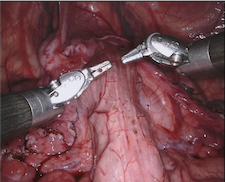

Our challenge was made up of 3 sub-problems. The first was binary instrument segmentation, where each frame was separated into da Vinci Xi instruments and a background class, which contained an ultrasound probe, surgical clips and porcine tissues. The second task was instrument part segmentation, where we scored the participants on whether they could correctly segment each articulating part of the instrument (see Fig. 3). Our final task was to segment and classify the instruments (see Fig. 4).

We provided the first 225 frames of 8 sequences as training data and kept the last 75 frames of those 8 sequences as test data. 2 of the full 300 frame sequences were kept as test sequences. Test labels were kept hidden from the participants. Our datasets contain 7 different robotic surgical instruments. The Large Needle Driver, Prograsp Forceps, Monopolar Curved Scissors, Cadiere Forceps, Bipolar Forceps, Vessel Sealer and additionally a drop-in ultrasound probe, which is typically held in the jaws of the Prograsp Forceps instrument. Samples from the training datasets are depicted in Fig. 2 and examples of the different instrument types are shown in Figure 3 and 4.

IV-D Type Segmentation

The final challenge was to identify each instrument type from the list of Large Needle Driver, Prograsp Forceps, Monopolar Curved Scissors, Vessel Sealer, Fenestrated Bipolar Forceps and Grasping Retractor (see Fig. 4). Only 6 teams participated in this challenge, due particularly to the significant increase in difficulty in recognizing many of the da Vinci instruments from one another.